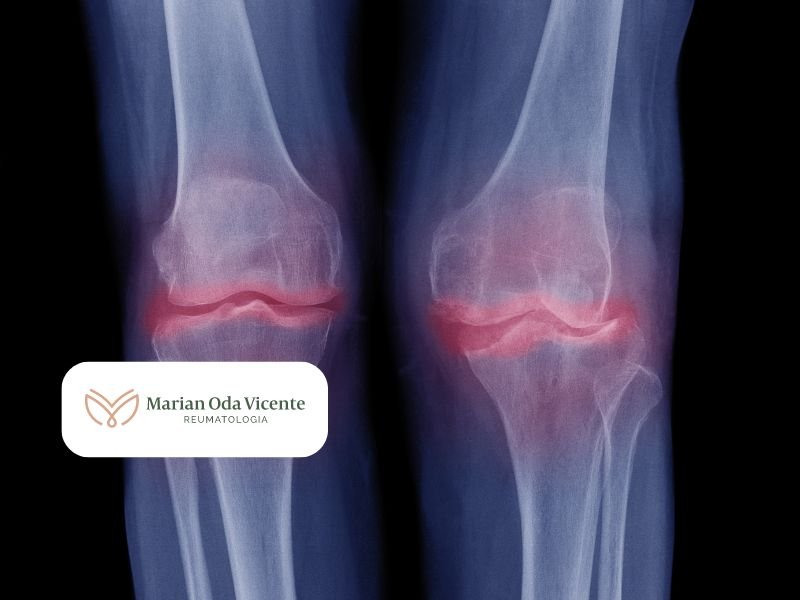

A osteoartrite é uma forma de artrite que ocorre quando o tecido protetor nas extremidades dos ossos (cartilagem) se desgasta com o tempo. Esta condição pode afetar qualquer articulação do corpo, mas ocorre mais frequentemente nas mãos, joelhos, quadris e coluna.

O diagnóstico geralmente é feito através de exame físico, avaliação dos sintomas e exames de imagem como raio-X ou ressonância magnética.